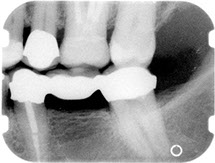

Before/After Photos